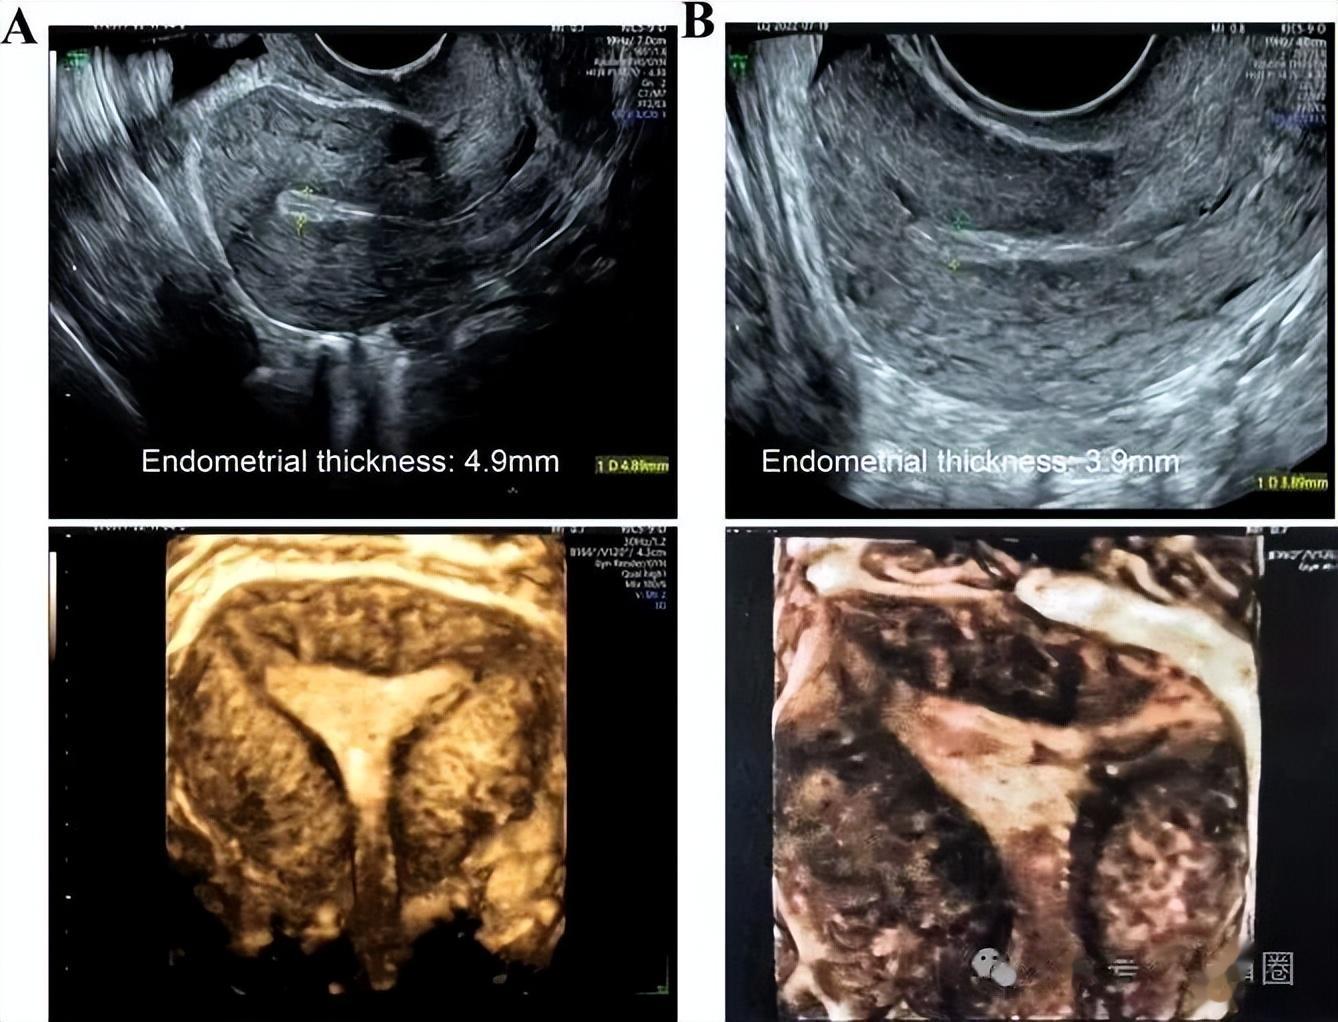

2022年7月,开始口服芬吗通,阴道使用西地那非,月经第18天内膜仅4.9mm,没有达标终止该周期治疗,尽管超声显示宫腔形态正常,内膜三线征清晰。

月经第14天,阴道三维超声显示内膜厚度仅3.9mm,另外提示宫腔粘连可能复发,只能停止治疗。